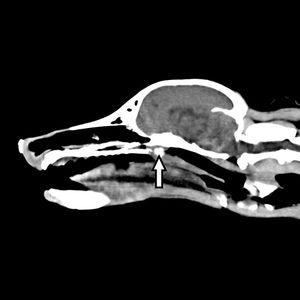

Discover which kind of disease this Labrador Retriever has, plus what causes the disease and how it is transmitted and treated.